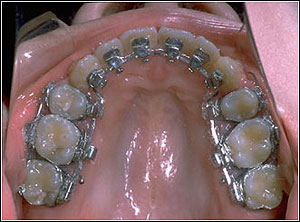

STEP 5. Detailing and finishing procedures

Stainless Steel with hook 016, 016*022, 017*025